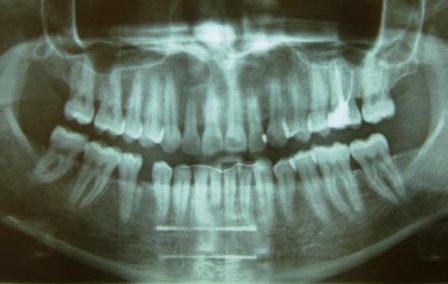

Ортопантомограмма - (панорамный снимок, ОПТГ) это изображение всех зубов костной ткани верхней и нижней челюстей, структуры гайморовой пазухи ,строения височно-нижнечелюстного сустава. Благодаря отображению изображения на компьютере, врач может приблизить каждый зуб и осмотреть его детально, оценить костную структуру челюстей (опухоли, переломы, кисты и др.), диагностировать воспаление гайморовой пазухи, смещение или перелом носовой перегородки, изменения строения височно-нижнечелюстных суставов.

ОПТГ используется различными специалистами-стоматологами: терапевтом, хирургом, пародонтологом, ортодонтом, ортопедом.